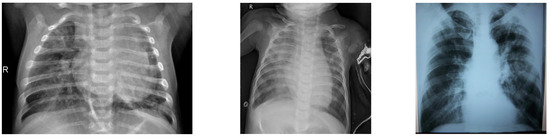

3.1. Dataset